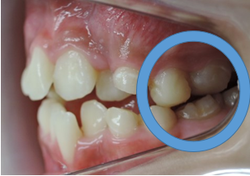

○印の中にある突起は永久歯の犬歯です。

但し、本来顎骨が劣成長であった場合はその中にある永久歯は著しい位置異常を起こしている場合が多い為に上下顎骨の大きさや咬み合わせの高さが改善したとしても、歯並びが悪くなる事がほとんどです。

その場合は永久歯の歯列矯正の計画の契約を結び永久歯の綺麗な歯並びと咬み合わせに改善していきます。